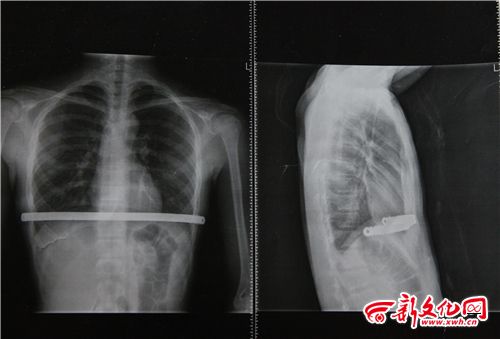

小博術后拍的CT片 本組圖片 新文化報 史磊 攝

家人懷疑小博的高燒與今年二月做的手術有關,因為患有漏斗胸,小博做手術在體內植入了鋼板。家人帶小博到北京的醫院檢查,檢查結果顯示各項指標都正常,不能確定小博高燒與之前的手術有關。